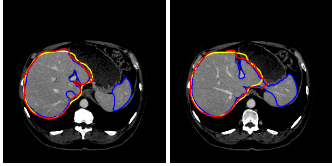

Refer to caption

Figure 1: Illustration of the challenges in automatic liver segmentation. The liver shares the similar intensity distributions with its surrounding organs (e.g., the right kidney and the spleen). The shape and appearance of the liver vary largely across subjects

Nevertheless, each of the existing techniques in the literature has limitations, when used on challenging cases. The main challenges may be summarized as follows. First, the liver shares the similar intensity distributions with its surrounding organs (e.g., the heart, the right kidney and the spleen). This makes it more challenging especially for automatic liver detection. Second, the shape and appearance of the liver vary largely across subjects. Finally, the presence of tumors or other abnormalities may result in serious intensity inhomogeneity. Figure 1 illustrates typical challenges as described above.